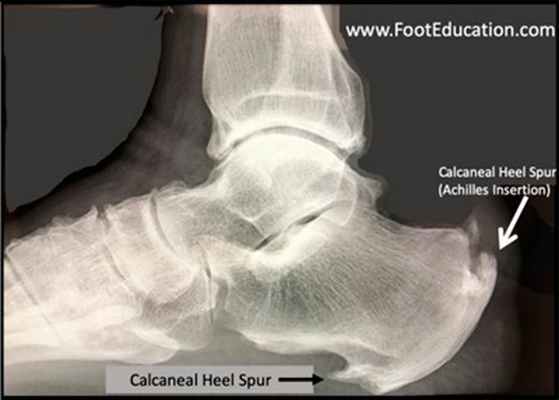

Пяточная шпора представляет собой остеофит пяточной кости. Этиологией шпор является наследственность, нарушения обмена веществ, туберкулез, ревматоидный артрит и системные воспалительные заболевания. К буграм пяточной кости прикрепляется множество мышц и подошвенная фасция, которые оказывают тракционное усилие на кость. Если пяточная шпора располагается на задней поверхности пяточной кости, то это дорсальная пяточная шпора, если она находится по подошвенной поверхности, то это подошвенная пяточная шпора. Дорсальные шпоры часто ассоциируются с тендинопатией ахиллова сухожилия, в то время как подошвенная шпора связана с подошвенным фасциитом. Вершина шпоры находится либо в месте прикрепления фасции на медиальном бугорке пяточной кости, либо в месте прикрепления мышцы короткого сгибателя пальца. Подошвенная фасция во время ходьбы претерпевает постоянное растяжение в связи с ритмичным опусканием и подъемом свода стопы, что приводит к хроническому растяжению апоневроза, которое предрасполагает к воспалительной реакции. Пронация стопы вызывает асимметричное натяжение подошвенной фасции. Избыточная пронация приводит к увеличению натяжения подошвенного апоневроза в месте прикрепления к бугру пяточной кости и считается основным механическим фактором развития подошвенной пяточной шпоры. Хроническая микротравма, которая вызывает разрывы подошвенной фасции вблизи ее прикрепления к кости, приводит к воспалению с дальнейшим развитием оссификации. Пяточная шпора прогрессирует в связи с длительным давлением на подошвенную фасцию и мышцы стопы, или растяжением подошвенной фасции вследствие избыточной подвижности 1 луча. Гиперподвижность структур медиального края стопы дает неравномерность натяжения подошвенной фасции. В области прикрепления фасции к пяточному бугру развивается хроническая микротравма и очаг воспаления, что приводит к развитию фасциита. По мере того, как воспалительный процесс приобретает черты хронического, развивается фиброз и оссификация в области пяточного бугра. Пяточная шпора может протекать либо бессимптомно, либо вызывать боль. Бессимптомные пяточные шпоры встречаются среди нормального взрослого населения в 11% случаев. Большинство пациентов с болью в пятке- это взрослые среднего возраста. У человека под пяткой появляется болезненный участок. Боль, которая локализуется в области медиального бугорка пяточной кости, вызвана давлением на подошву стопы в области прикрепления подошвенного апоневроза к пяточной кости.

Шпоры разделены по характеру течения. Во-первых, это шпоры с незначительной воспалительной реакцией с нечеткими, нерегулярными, неровными контурами с пониженной плотностью кости в области прикрепления подошвенной фасции на рентгенограмме. Они характерны для начала патологического процесса. Во-вторых, это шпоры большого размера, прогрессирование которых связано с весовой нагрузкой. Они протекают бессимптомно в связи с прекращением воспалительного процесса. В-третьих, это большие шпоры, которые вызывают боль в связи с постоянной нагрузкой, вызванной продольным или поперечным плоскостопием, вальгусом пятки и гиперпронацией стопы.

Рис. 7. Рентгенограмма стоп. Пяточная шпора